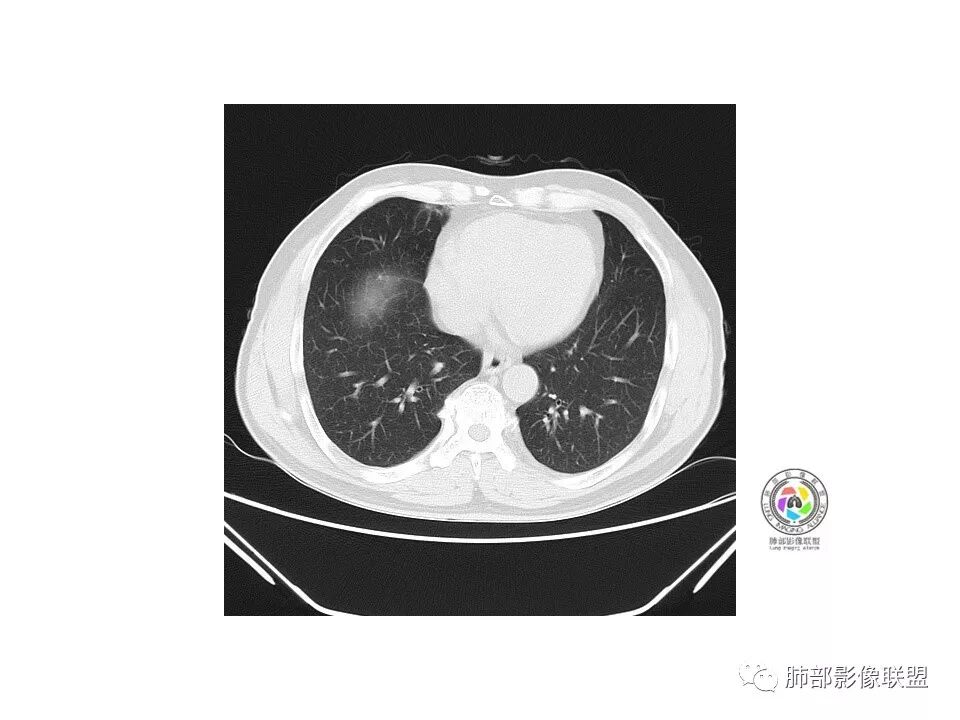

右肺下叶混合磨玻璃密度结节,有月牙铲,内可见血管,血管移动联通,常规消炎复查,还存在考虑AIS-MIA

go and see:

患者老年男性,右下肺前基底段靠近胸膜侧可见一个mGGO结节,边缘清淅,可见分叶征及月牙铲,小结节病灶胸膜牵拉明显,首先考虑MIA可能性大。

弹指之间:

右肺下叶mGGO,边缘清晰,浅分叶,内血管影增粗,见点状实性成分,小支气管牵拉扩张,考虑MIA,建议抗炎后复查。

张小兵:

右肺下叶前基底段mGGN,边界清晰,内部结构杂乱,见网格空泡感,月牙铲,浅分叶及胸膜牵拉,倾向MIA。

Shelia??:

右肺下叶GGO,边缘清晰,有月牙铲,有血管进入,内部结构紊乱,胸膜牵拉,考虑MIA,常规建议抗炎治疗后复查。

崇军:

右肺下叶磨玻璃结节,边界清晰,边缘有分叶及月牙铲,并可见轻度胸膜牵拉,收缩力弱,有血管移动联通征,而且病灶内血管影轻度增粗,实性成分很少,考虑AIS,可以让子弹再飞一会,或常规抗炎治疗后复查。

欣:

界清ggo,月牙铲,考虑腺癌

欧阳英:

右肺下叶前基底段磨玻璃小结节,其内血管稍增粗,边缘见分叶、月牙铲,考虑ais,炎性结节不排

南边老师分析

是GGN吗?边界清吗?收缩力?

丽:

边界清,收缩力强

南边:

血管如何?

血管似有增粗

有增粗,联通、移动,高度怀疑Ca,常规抗炎后复查

病理结果

腺癌